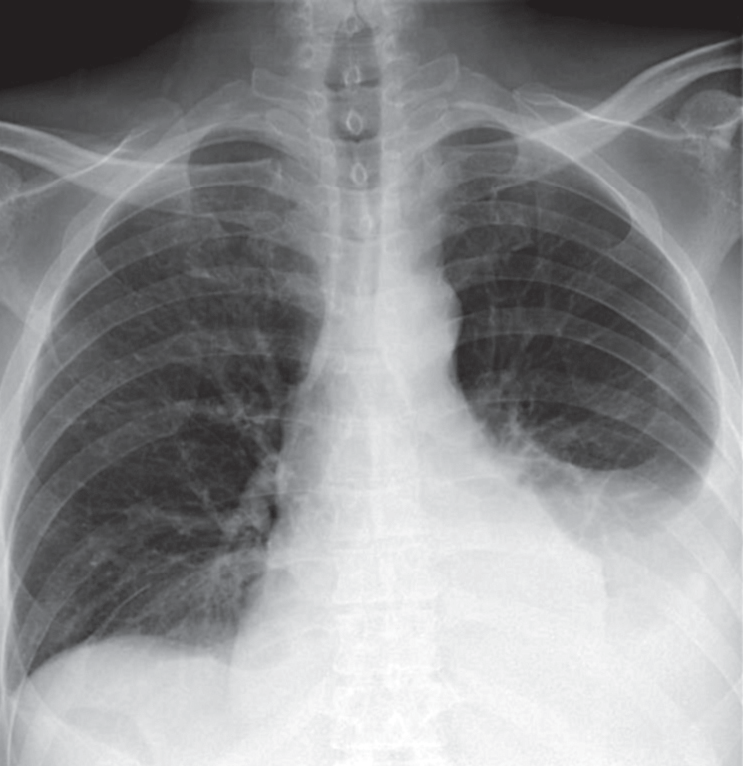

В приемном отделении стационара при осмотре состояние было оценено как тяжелое, выявлен цианоз губ, при аускультации над легкими – везикулярное дыхание, справа в нижних отделах ослаблено, там же выслушиваются мелкопузырчатые хрипы. ЧДД – 20 в минуту. Тоны сердца приглушены, аритмичны. ЧСС – 140 в минуту. АД – 100/60 мм рт. ст. Живот мягкий, безболезненный. Голени пастозны. Выполнена рентгенография грудной клетки, по результатам которой выявлена правосторонняя нижнедолевая пневмония и жидкость в обеих плевральных полостях (рис. 1). На ЭКГ: фибрилляция предсердий с ЧСЖ 120–200 в минуту. Неполная блокада ПНПГ, синдром sI-qIII.

Рис. 1. Рентгенограмма пациента Г. при поступлении в стационар